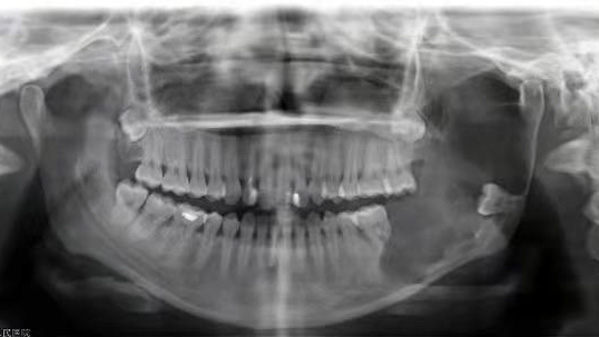

患者小張(化名)是一位年輕女性,因左側(cè)下頜骨漸大2月余到我院口腔科就診,檢查后被確診為下頜骨成釉細胞瘤,該腫瘤多發(fā)生在下頜骨,以下頜體、下頜角多見,腫瘤進一步發(fā)展可侵犯周圍軟組織。

據(jù)口腔科副主任醫(yī)師劉彥杰介紹,由于患者腫瘤侵襲的范圍較大,徹底治療只能截斷下頜骨切除腫瘤。但這就意味著,術(shù)后將會出現(xiàn)明顯的面部塌陷,即便用軟組織修復(fù),也會影響面部和口腔功能進食、說話都受影響……